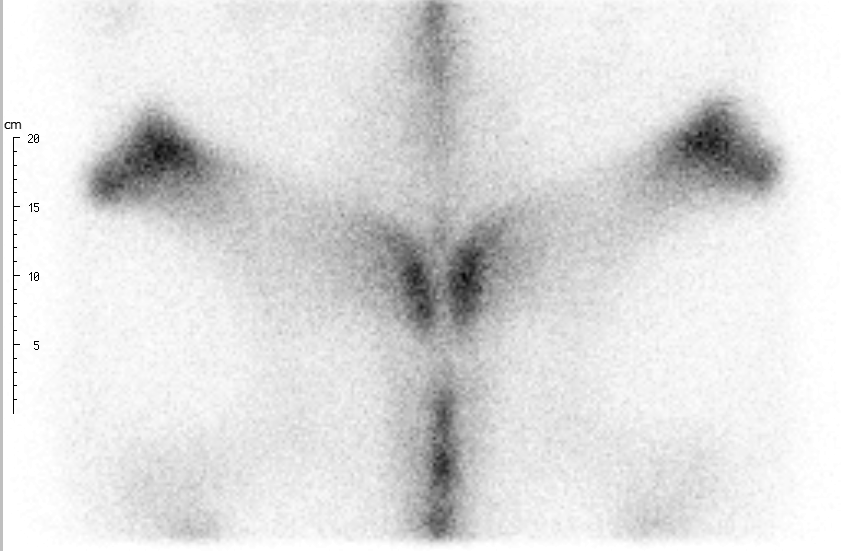

Real-Time Motion Correction: Faster Scans, Enhanced Quality

ParalyzerPLUS

ParalyzerPLUS raw study

raw study ParalyzerPLUS

ParalyzerPLUS raw study

raw study ParalyzerPLUS

ParalyzerPLUS raw study

raw study ParalyzerPLUS

ParalyzerPLUS raw study

raw studySelection of possible studies